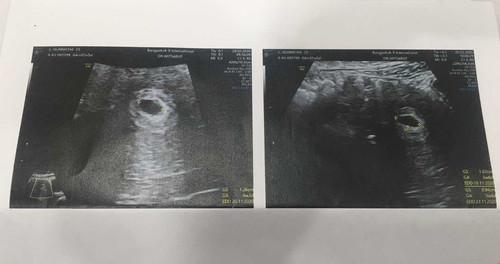

อายุครรภ์คร่าวๆน่าจะ1เดือน แบบนี้ปรกติมั้ยคับ